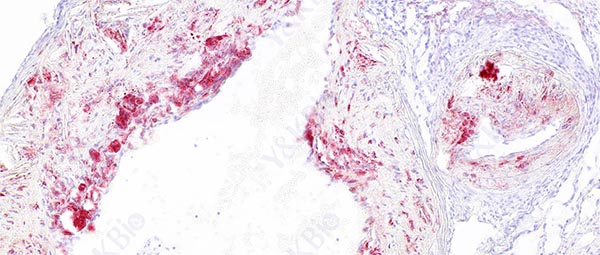

云南冰冻切片是一种常见的组织学技术,用于制备组织标本以供显微镜观察。为了预防冰晶形成,可以采取的措施包括适当固定组织、适当处理组织、使用适当的冷冻介质、控制切片速度、注意环境温度和湿度等。